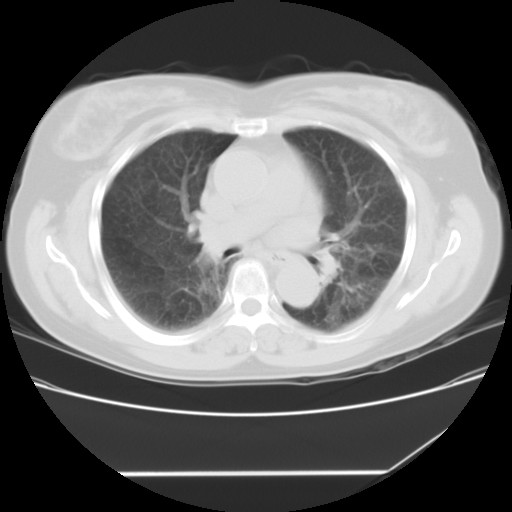

间质性肺炎,有纤维化趋势。

1)慢性支气管炎并肺部感染、肺气肿。2)肺间质纤维化。

间质性肺炎,左下肺机化性肺炎。